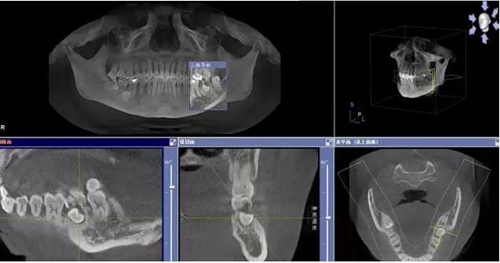

圖1.術前的CBCT檢查:37頰側部分牙根被完全壓迫吸收。

1.jpg